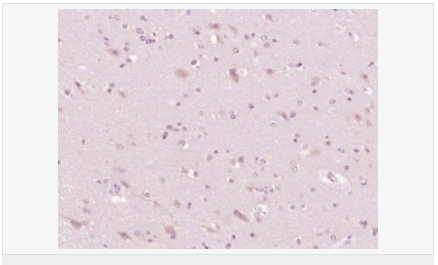

image.png